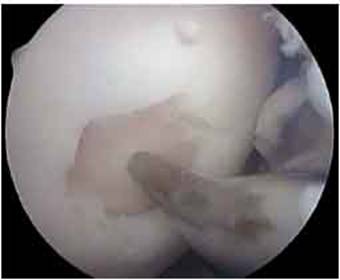

Fig.18. Secvente din timpul operatiei cu artroscopul

Artroscopia arata repararea tesuturilor la sase saptamani.